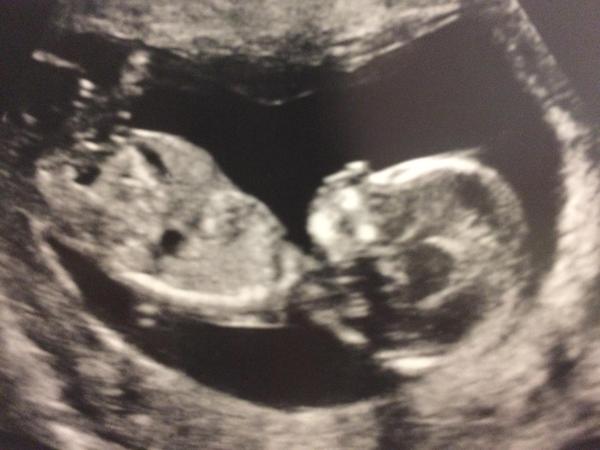

Tomkat79 · 08/04/2016 13:55

Well hello number 3! So relieved!